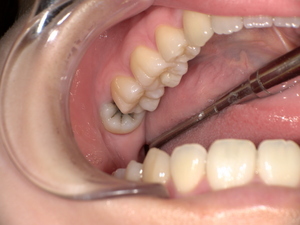

Before(下親知らずの抜歯前) 横に生えた状態で埋まっている親知らず 虫歯がある親知らず 抜歯前の骨の状態のレントゲン像

拝見したところ、一部分のみ生えている左下の親知らず(第3大臼歯/8番)と左下の奥歯(第2大臼歯/7番)との間で、歯肉の腫れが認められました。